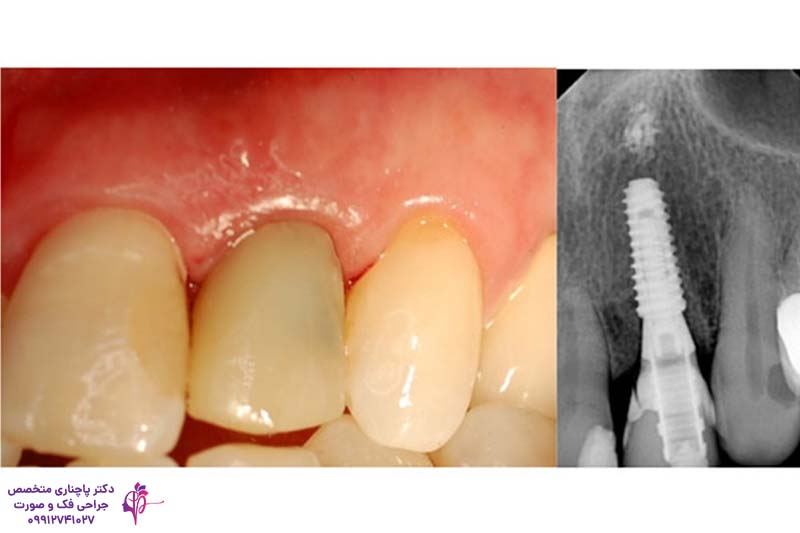

عکس لترال دندان همان عکسی است که قبل از شروع درمان باید بگیرید تا مشکلات آن مشخص شود. قبل از شروع درمان برای اینکه وضعیت استخوان فک در این ناحیه مشخص شود برای این کار از عکسهای رادیوگرافی یا تصاویر سه بعدی استفاده میکنند. این عکسها حتی پوسیدگیها و شرایط ریشههای دندانهای مجاور را هم نشان میدهند. یک سری عکس هم از نزدیک برای بررسی تقارن دندانها، رنگ و شکل لثه گرفته میشود. این عکسها هم برای ساخت تاج و روکش دندان لترال مهم هستند.

ایمپلنت دندان لترال بهترین و موثرترین روش برای پر کردن جای خالی دندان لترال است. پایه تیتانیومی ایمپلنت جای ریشه این دندان را در فک میگیرد و بعد هم یک روکش همرنگ دندان رویش نصب میشود و اصلا کسی متوجه مصنوعی بودن دندان نمیشود. روکش دندان لترال از مواد سرامیکی یا زیرکونیا ساخته میشود و علاوه بر استحکام عالی ظاهری طبیعی به دندانها میدهد.

یکی از نکات کلیدی در ایمپلنت دندان لترال، شکلدهی درست و متقارن لثه است، چون کوچکترین ناهماهنگی در خط لثه یا برجستگی پاپیلا بلافاصله در لبخند مشخص میشود. یک موضوع مهم دیگر در فرآیند کاشت نازک بودن بافت لثه در این قسمت است. احتمال اینکه یک هاله تیره از پایه تیتانیومی از روی لثه دیده شود بالاست به همین دلیل بعضی دندانپزشکان از روکشهای سفارشی و اباتمنتهای زیرکونیای سفید استفاده میکنند تا این سایه تیره حذف شود.

نصب روکش ایمپلنت لترال مرحله نهایی کاشت ایمپلنت دندان است. بعد از اینکه فرآیند ادغام پایه و استخوان کامل میشود، دندانپزشک از دندان قالبگیری میکند و ساخت روکش به صورت سفارشی در آزمایشگاه انجام میشود. این روکش معمولا از جنس سرامیک یا زیرکونیا ساخته میشود تا با دندانهای مجاور همخوانی داشته باشد. این روکشها معمولا با پیچ به پایه متصل میشوند. بعد از نصب دندانپزشک لثه اطراف روکش را با ابزارهای ظریف شکی میدهد تا ناحیه پاپیلا طبیعی به نظر برسد.